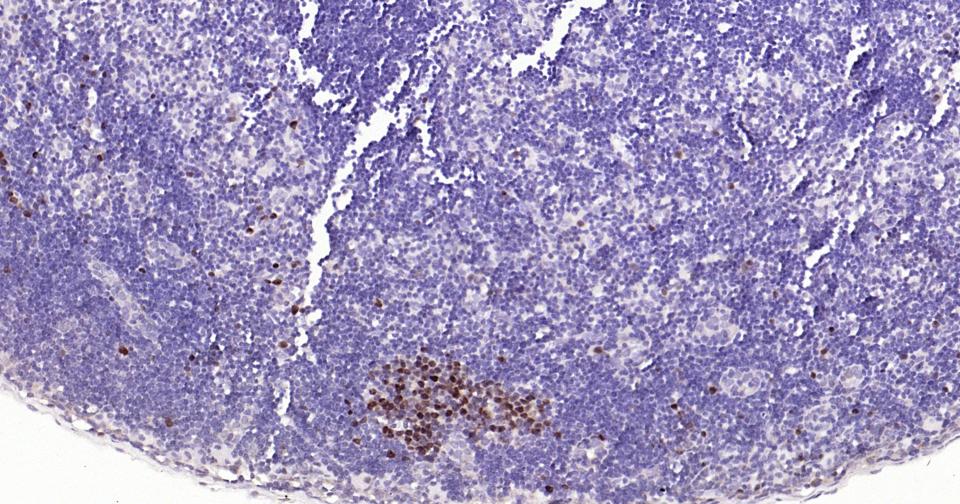

Paraformaldehyde-fixed, paraffin embedded Rat Lymph; Antigen retrieval by boiling in sodium citrate buffer (pH6.0) for 15 min; Antibody incubation with TOP2A Monoclonal Antibody, Unconjugated(bsm-61077R) at 1:400 overnight at 4°C, followed by conjugation to the SP Kit (Rabbit, SP-0023) and DAB (C-0010) staining.

Paraformaldehyde-fixed, paraffin embedded Mouse Lymph; Antigen retrieval by boiling in sodium citrate buffer (pH6.0) for 15 min; Antibody incubation with TOP2A Monoclonal Antibody, Unconjugated(bsm-61077R) at 1:400 overnight at 4°C, followed by conjugation to the SP Kit (Rabbit, SP-0023) and DAB (C-0010) staining.